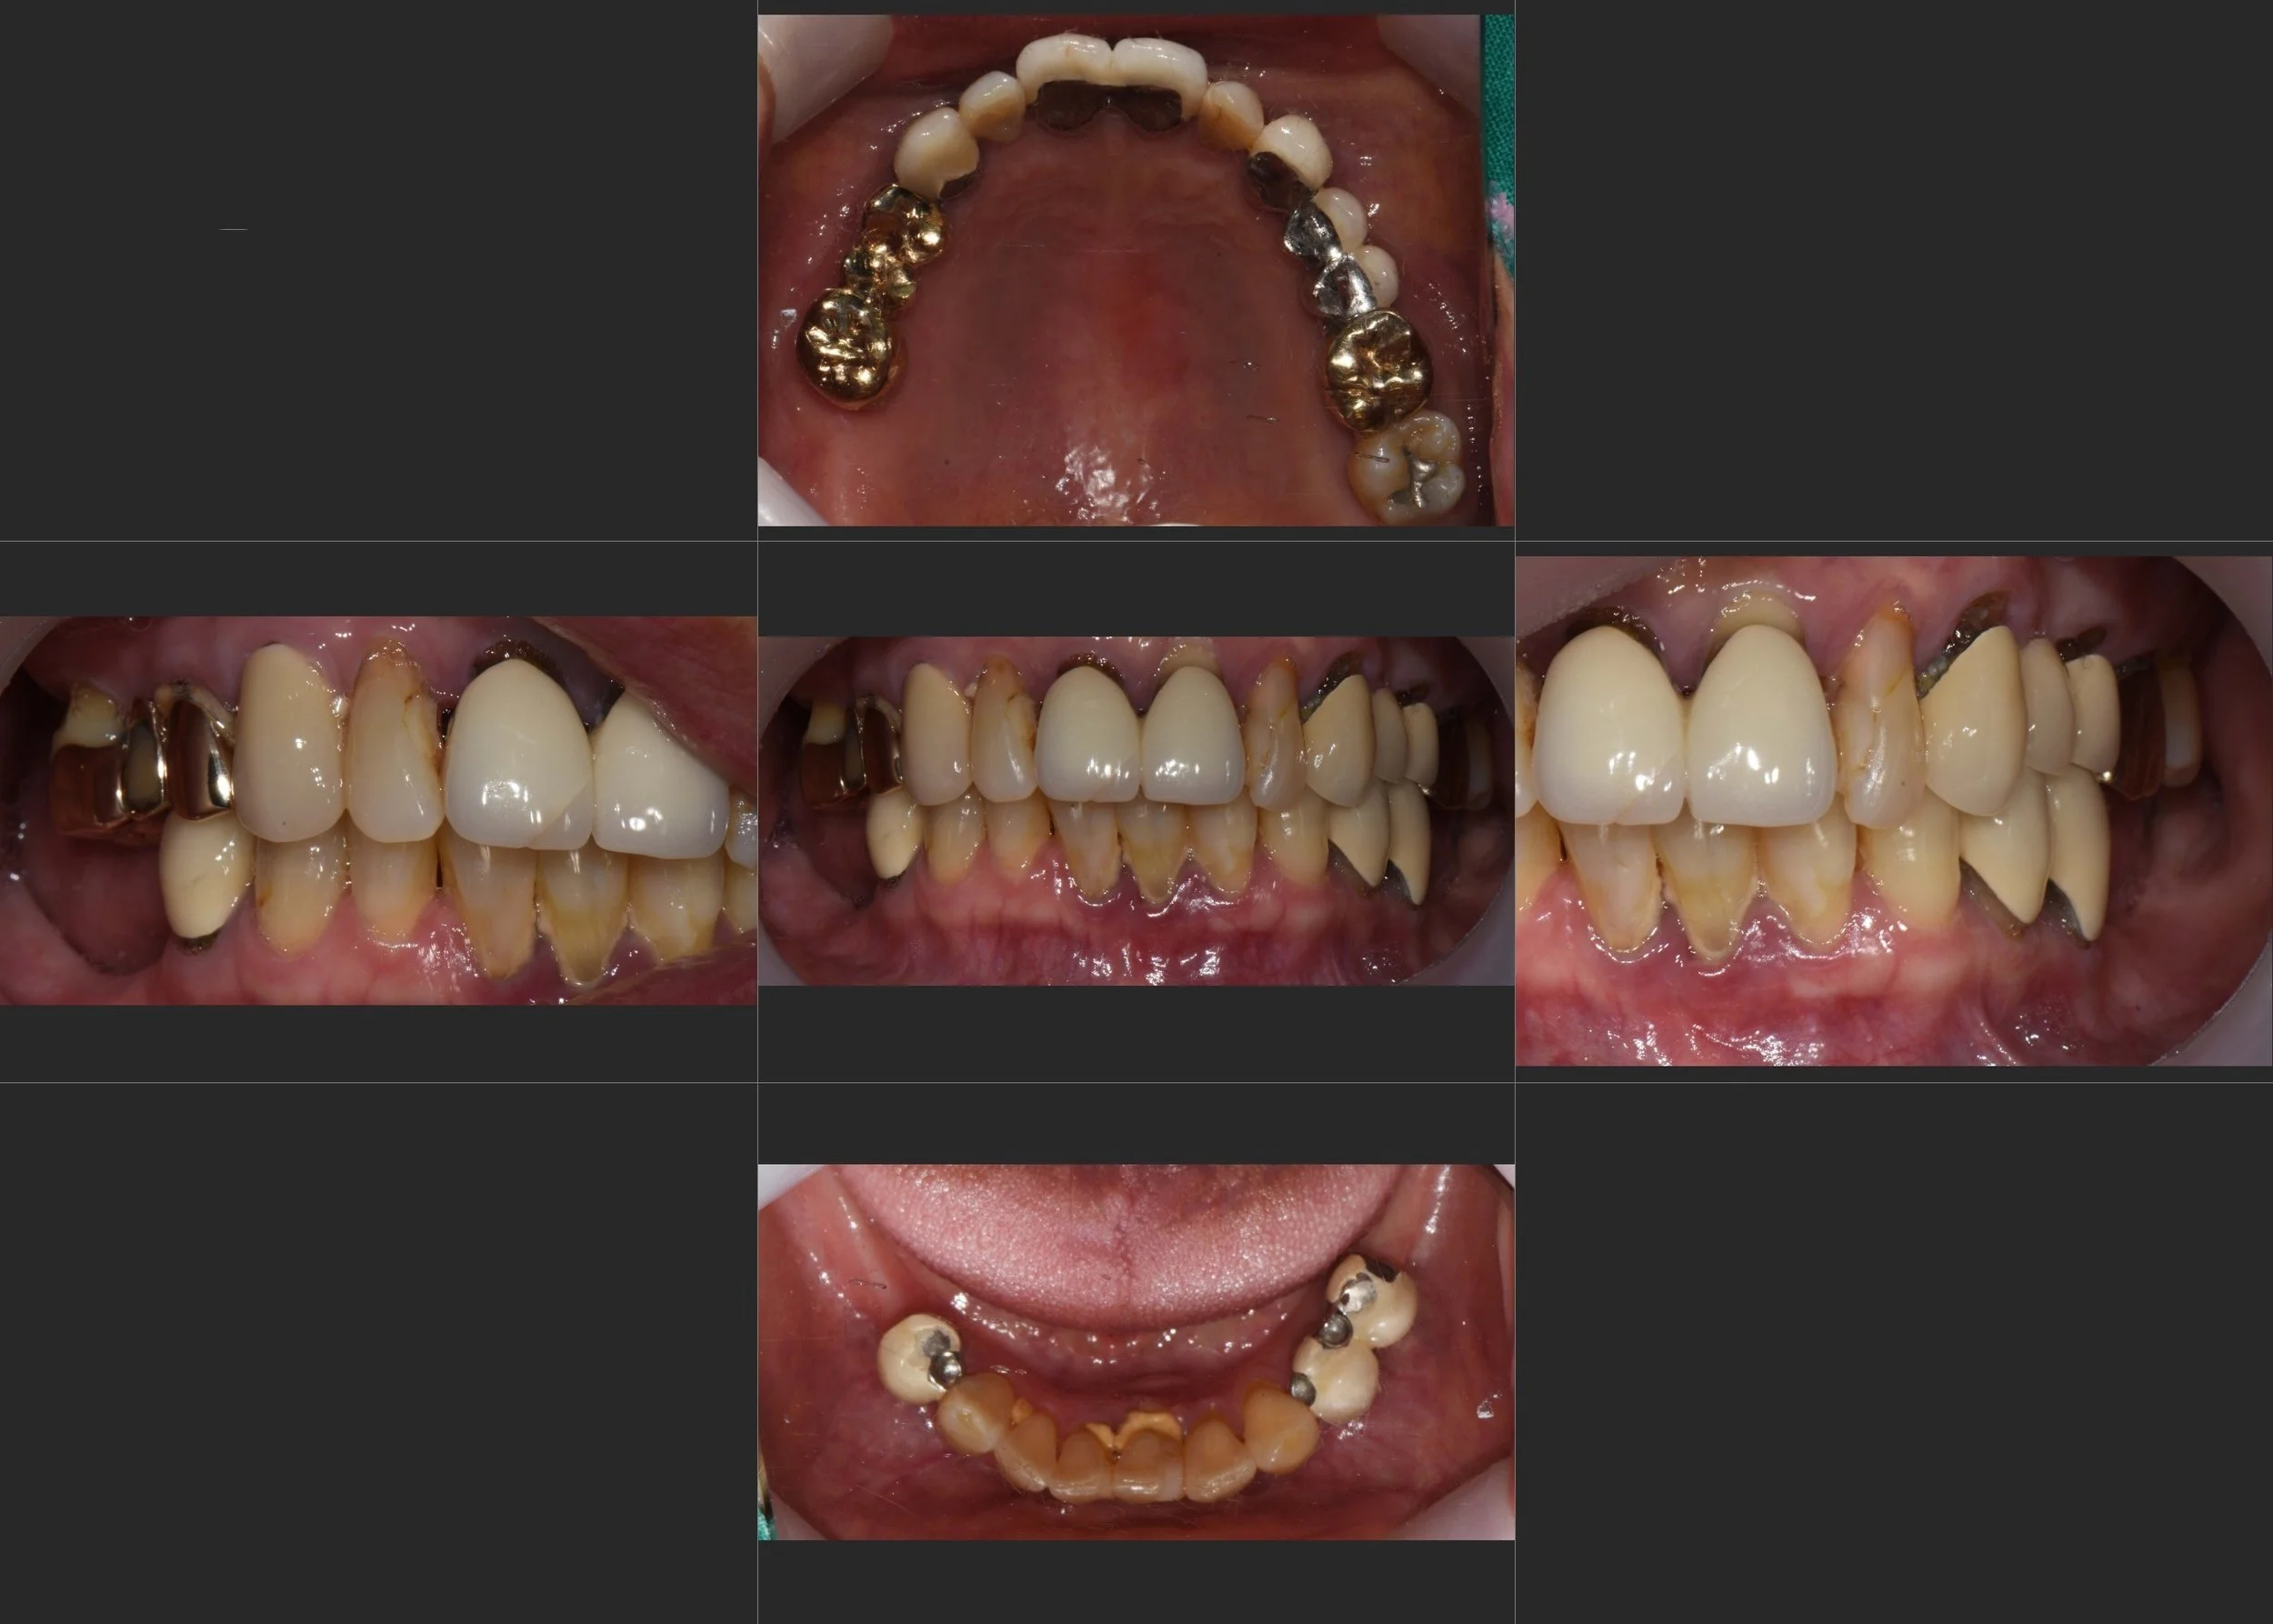

INTRA ORAL - AFTER

3. Prosthetic Reconstruction: Once stability was confirmed, definitive zirconia implant-supported bridges and crowns were delivered. Particular attention was paid to the "emergence profile" and crown contouring to ensure the patient could easily perform oral hygiene.

4. Maintenance Protocol: The final occlusal scheme was designed to be "maintenance-friendly," focusing on easy access for interdental cleaning, which is vital for patients with a history of severe periodontitis.

The patient successfully transitioned from the discomfort of failing dentures to the security of a fixed, functional, and aesthetically pleasing dentition.